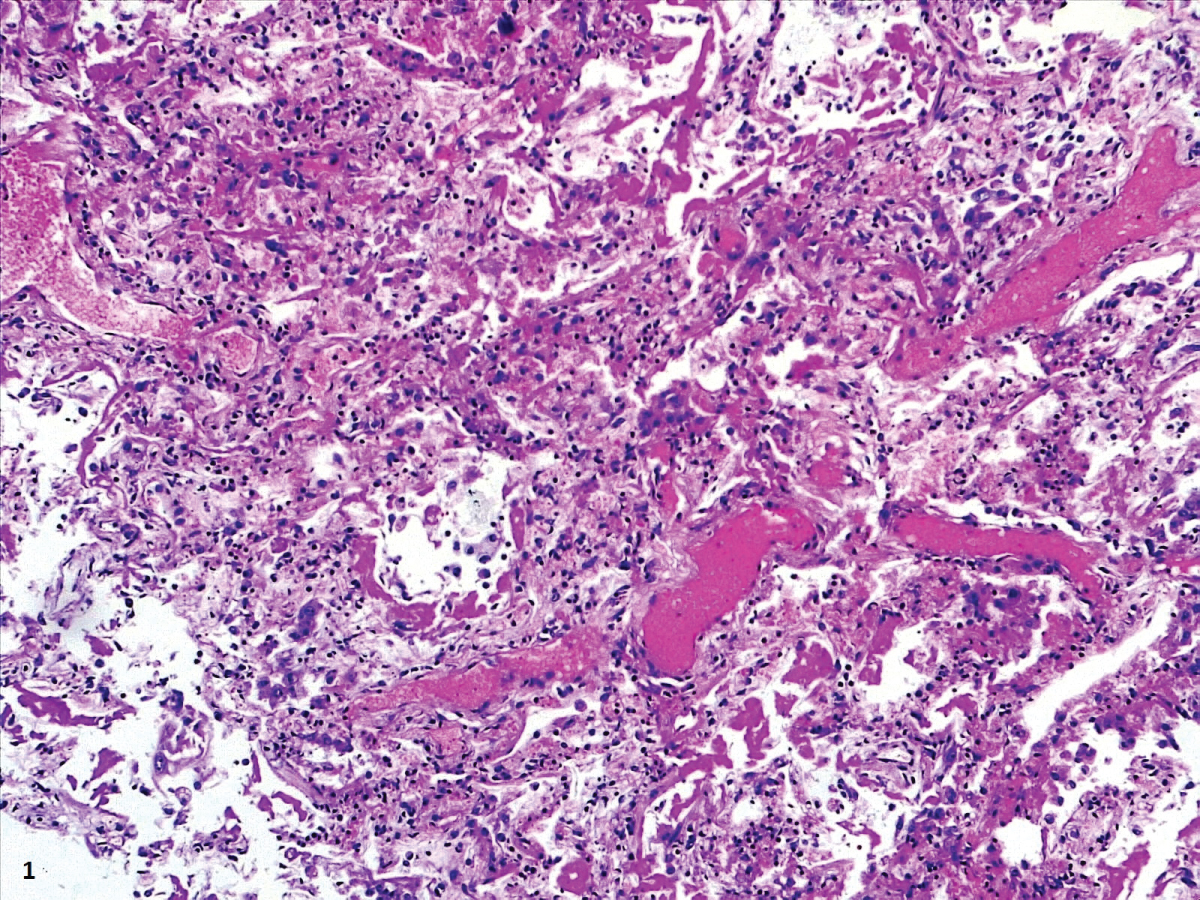

In our cases, we observed markedly congested vessels (Figure 1), and prominent DAD with coexistence of exudative and proliferative phases in most patients (Figure 2 and Figure 3). In the periphery of the more compromised areas, the presence of alveolar microthrombi was striking. The immunohistochemistry with TTF-1 highlighted the hyperplasia of atypical type II pneumocytes (Figure 4); and with CK7 collapsed alveoli were surrounded by a fibroblastic proliferation (Figure 5). As it was observed by others, we found scant inflammatory infiltrates in the majority of cases, but those complicated by bronchopneumonia (Figure 6). We also found giant multinucleated cells, which were positive to CK7, and had cytopathic-like changes in the majority of cases (Figure 7). The cytopathic-like changes consisted of large nuclei, nucleolar inclusions, lumpy chromatin, and a large, eosinophilic cytoplasm; however, these changes are not specific for Sars-cov-2, therefore they cannot be used as diagnostic criteria for COVID-19 pneumonia. Variable amounts of CD68 positive alveolar macrophages were identified (Figure 8). Interestingly, higher amounts of alveolar macrophages were observed in patients with the highest values of ferritin (observation not systematized). This finding correlates with the role of ferritin in macrophage activation and the proposal to include COVID-19 within the hyperferritinemic syndromes [38].

Figure 2: Prominent DAD with coexistence of exudative and proliferative phases. View Figure 2